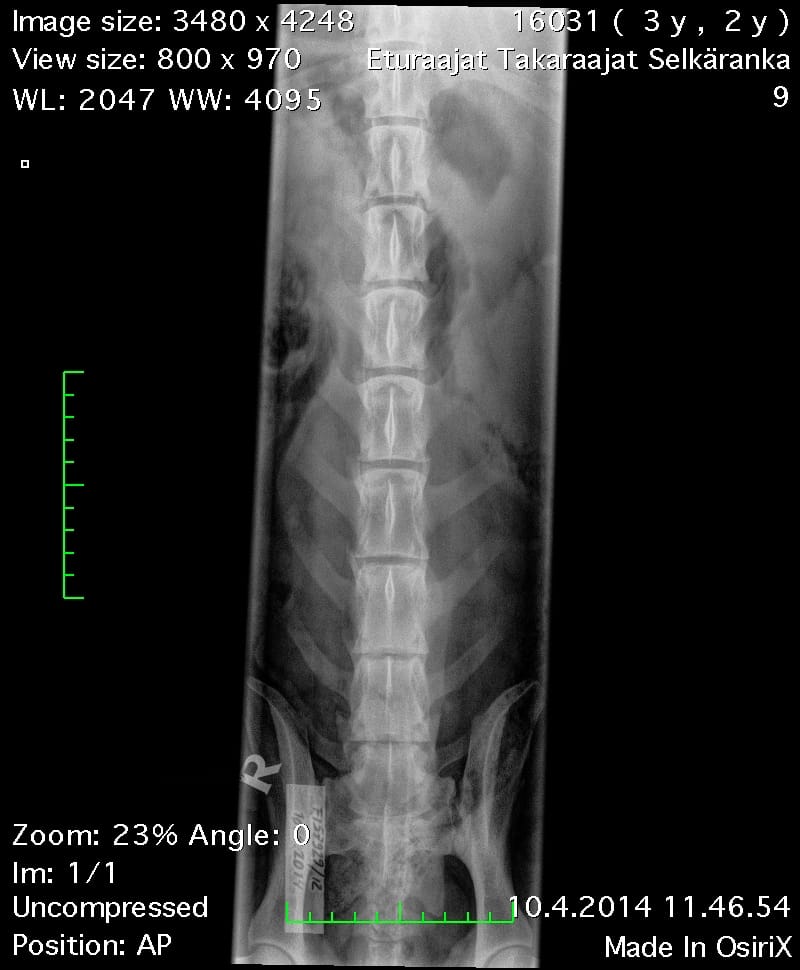

| Shoulders: | clear | |

| Spine: | SP0, LTV4 (8 lumbosacral vertebrae) | |